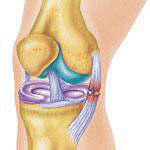

The Ligament Damaged in this Image. (OK for Abbr...but must be able to say what it stands for)

MCL (Medial Collateral Ligament)